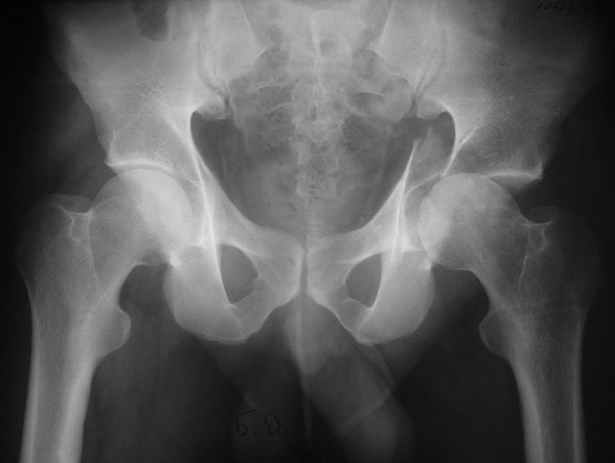

Высылаю пример еще одного случая, остеосинтез пластиной из подвздошного доступа.

Анатолий, во второй презентации, какой Ваш диагноз, не поперечный ли перелом ацетабулум? Вы написали, Ваш доступ был подвздошный, по моему мнению, ваш доступ лимитировал Вас к anterior column и постоянно надо было держать в контроле за натяжением femoral artery and vein, иначе грозит закупоркой артерии или вены, (были и такие experience), при сгибании в тазобедренном суставе, которое ухудшает и так ухудшенный доступ. По-моему, если доступ расширить, т.е. formal Ilioinguinal approach то применить пластину подлиннее 12-14 дырок на pelvic brim, через первое окно Ilioinguinal approach, т.е. Symphisis side, после рассечения места прекрепления muscle rectus abdominus, где достаточно места для 4 шурупов, тогда таким образом фиксированный перелом держится более стабильно и 4.5 мм шурупы для колонн можно было бы пропустить через пластину кзади впадины.